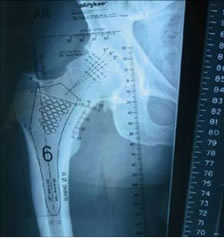

| Pre-op templating |

His own templating process |

Determining neck resection |

Photos from His First Case

Dr. Mackel has participated at cadaver training, observed live surgery and has studied and reviewed the design concept, surgical technique and attended educational seminars prior-to scheduling his first case. It is this dedication to this educational process that reduces his operative learning curve and provides his patients with the best possible clinical/surgical outcome. |

JISRF is pleased that Dr. Mackel has agreed to help define the indications and contraindications on Neck Stabilized Stems for THA and as part of that process, what are the learning curves to preoperative planning (templating). Lateral templating appears to be key in determining stem size and A/P helps to determine level of neck resection (leg length) and femoral offset. |